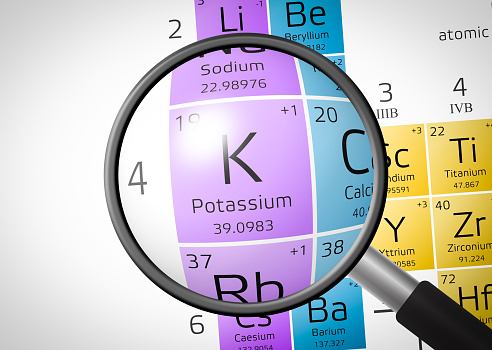

How does potassium lower blood pressure?

When it comes to healthy blood pressure, you need to balance your intake of sodium and potassium. High blood pressure, or hypertension, is when the pressure of blood flow pushes against the veins. High blood pressure can contribute to other major heart events and even stroke. High blood pressure can be symptomless, and if not ...click here to read more